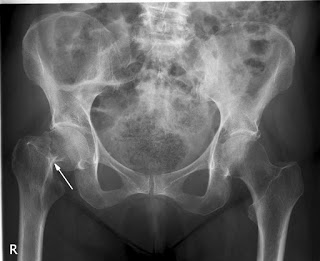

Cirugía de cadera ultrarrápida

02 marzo 2020